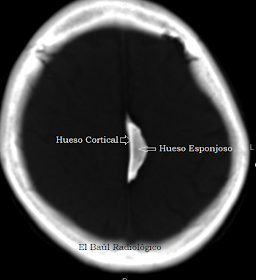

La osificación fisiológica de la hoz del cerebro, en la cisura interhemisférica frontal, es un hallazgo muy frecuente en las imágenes de Tomografía Computarizada craneoencefálica realizadas a personas mayores, por otros motivos. Es siempre un hallazgo incidental. Suele presentarse como una o varias imágenes hiperdensas, alargadas, de aspecto parecido al de una semilla de girasol, con un borde plano, el que contacta con la duramadre. Aunque se definen erróneamente como "calcificaciones de la hoz" no lo son. La osificación es una neoformación benigna, de etiología desconocida, que da lugar a un pequeño fragmento de hueso vivo en el que se distinguen: un núcleo central de hueso esponjoso contorneado por una lámina de hueso compacto cortical.

Se desconoce el mecanismo fisiológico que desencadena este proceso en una estructura anatómica, como la hoz del cerebro, que habitualmente no contiene tejido óseo. Parece ser que algunas de las células mesenquimatosas que forman las membranas de tejido conjuntivo de la hoz se convierten en osteoblastos que constituyen un núcleo de osificación alrededor del cual se va formando hueso. En una segunda fase la matriz ósea se calcificará formando los tabiques del hueso esponjoso. Posteriormente las lagunas óseas se irán rellenando de médula roja y tejido adiposo. Con la edad se produce la sustitución fisiológica de la médula roja por grasa que ocupa todo el fragmento osificado. Éste cúmulo anómalo de grasa será la causa de algunos errores diagnósticos. En las siguientes imágenes presentamos algunos casos demostrativos.